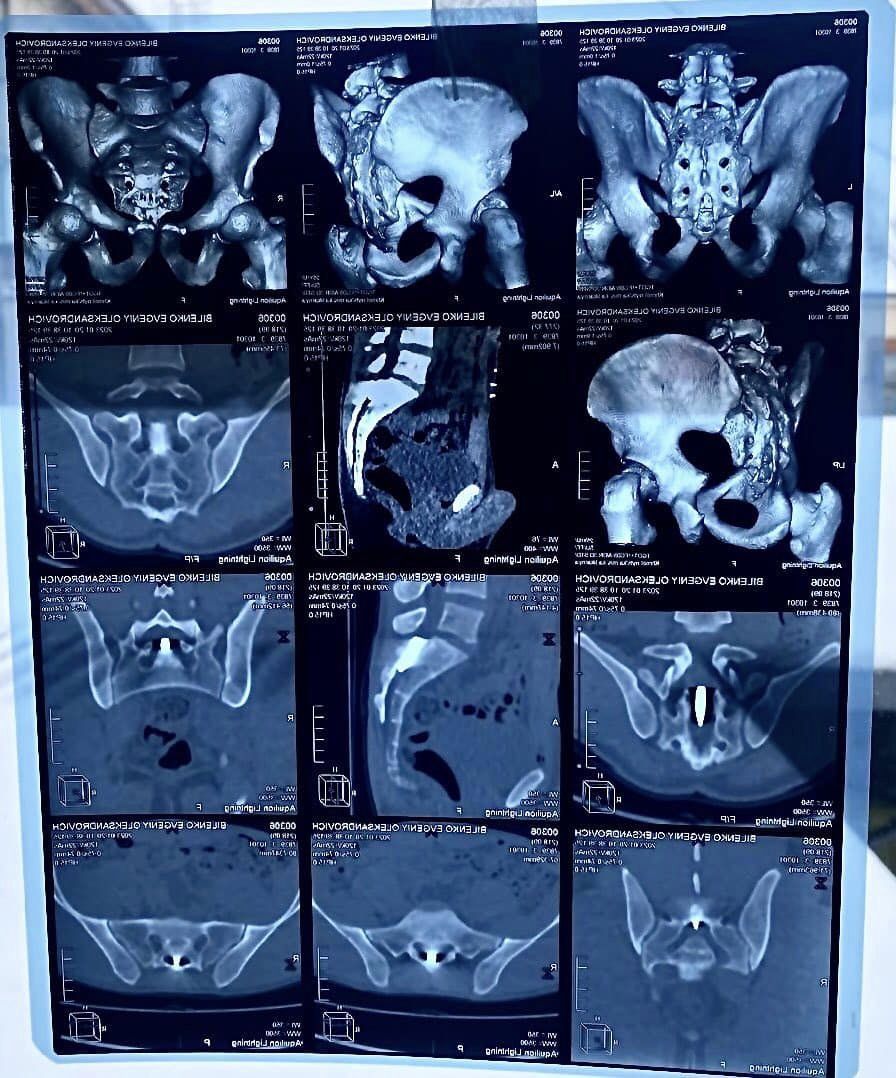

Медики зазначають, що під час бойових дій захисник отримав вогнепальне поранення. Куля калібром 7.42 пройшла через живіт та опинилась у попереково-крижовому відділі хребта. Вона пробила тверду мозкову оболонку, поміняла траєкторію вниз, і застрягла у попереку, між сакральними нервовими закінченнями, які відповідають за рухи тазу та нижніх кінцівок.

— Складність оперативного лікування в тому що куля у середені огорнута у так звану «біоплівку», в яку також були окутані нервові корінці, які виконують важливі неврологічні функції. Розмір яких у діаметрі 1-2 мм, і мають дуже ніжну структуру, — пояснюють в закладі.